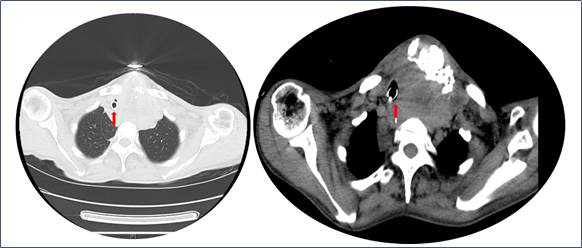

2020年12月5日,患者颈部CT可见明显肿物,并压迫气道(图1)。另外,患者胸部CT可见气道因肿物压迫已经发生了偏移(图2)。

图1 患者颈部CT(2020-12-05)

图2 患者胸部CT(2020-12-09)